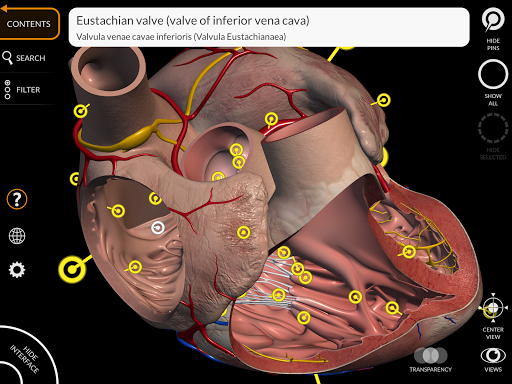

"Anatomy 3D Atlas" memungkinkan Anda mempelajari anatomi manusia dengan cara yang mudah dan interaktif.

Melalui antarmuka yang sederhana dan intuitif, Anda dapat mengamati setiap struktur anatomi dari sudut mana pun.

Model 3D anatomi sangat terperinci dan memiliki tekstur hingga resolusi 4k.

Pembagian berdasarkan wilayah dan tampilan yang telah ditetapkan sebelumnya memudahkan pengamatan dan studi bagian tunggal atau kelompok sistem dan hubungan antara organ yang berbeda.

MODEL ANATOMI 3D

• Sistem kardiovaskular • Sistem

saraf • Sistem pernapasan • Sistem pencernaan • Sistem urogenital (pria dan wanita) • Sistem endokrin • Sistem limfatik • Sistem mata dan telinga FITUR • Antarmuka yang sederhana dan intuitif • Putar dan perbesar setiap model dalam ruang 3D • Opsi untuk menyembunyikan atau mengisolasi satu atau beberapa model yang dipilih • Filter untuk menyembunyikan atau menampilkan setiap sistem • Fungsi pencarian untuk menemukan setiap bagian anatomi dengan mudah • Fungsi penanda untuk menyimpan tampilan khusus • Rotasi cerdas yang menggerakkan pusat rotasi secara otomatis • Fungsi transparansi • Visualisasi otot melalui tingkat lapisan dari yang superfisial hingga yang terdalam • Dengan memilih model atau pin, istilah anatomi terkait akan muncul • Deskripsi otot: asal, • Tampilkan/ Sembunyikan antarmuka UI (sangat berguna dengan layar kecil) MULTIBAHASA • Istilah anatomi dan antarmuka pengguna tersedia dalam 11 bahasa: Latin, Inggris, Prancis, Jerman, Italia, Portugis, Turki, Rusia, Spanyol, Mandarin, Jepang, dan Korea • Istilah anatomi dapat ditampilkan dalam dua bahasa secara bersamaan PERSYARATAN SISTEM • Android 8.0 atau yang lebih baru, perangkat dengan RAM minimal 3GB Reversi

• Fungsi penanda untuk menyimpan tampilan khusus